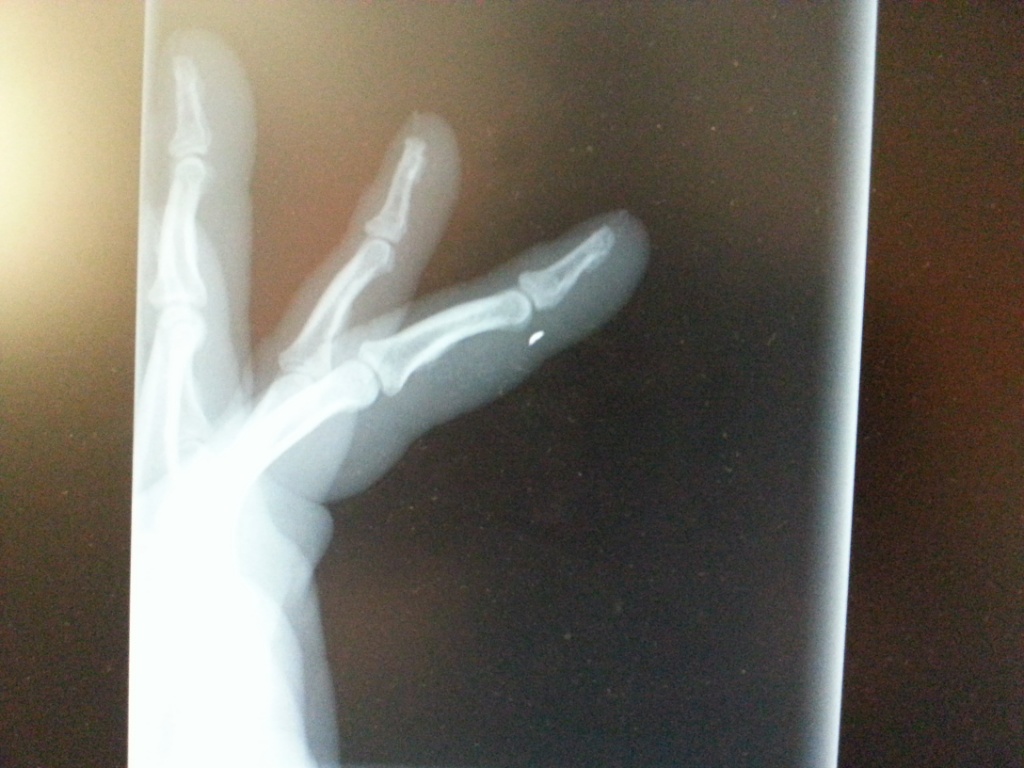

Ne nadarmo se rika, ze tak dlouho se chodi se dzabanem pro vodu....

A ja moc dobre vim ze mlatit kladivem do kladiva se nema jelikoz se muze odstipnout, jen mne nikdy nenapadlo ze ta strepinka bude jak projektil. Vysledny efekt je rozparana ruka resp. prst od doktora a dalsi nove stehy k tem stavajicim.

IMG_20130929_021640.jpg

IMG_20130929_021640.jpg (212.26 KiB) Zobrazeno 2987 krát

Frankie, ano, smula, ale jeste pri tom vsem stesti, ze to neletelo do oka... :(